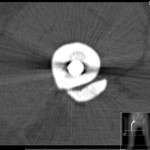

She was initially investigated with plain radiographs and this did not show any obvious pathology. Therefore, further investigation with MRI magnetic resonance imaging was requested of the left shoulder. . The MRI scan showed signal changes within the deltoid muscle consistent with diffuse oedema on the proton density weighted sequence and there was no evidence of plexiform neurofibroma (Fig. 1).

She underwent nerve conduction and electromyography studies and the results were within normal limits in particular excluded an axillary nerve lesion, with axillary nerve M-wave apmplitude of 14.1 and terminal latency of 3.3 with normal motor action potentials seen within the deltoid. This confirmed the absence of an axillary nerve lesion. There was an intitialinitial elevation in erythrocyte sedimentation rateESR (26 – 73 mm/h) and C reactive proteinCRP of 12;, however, they returned to normal parameters when her symptoms abated. . The patient was screened thoroughly to rule out connective tissue disorders with antinuclear, antineutrophil cytoplasmic antibodies,ANCA and extractable nuclear antigen (ENA) antibody panels, as well as diabetes. . Blood investigations for creatine kinase and lactate dehydrogenase levels taken during the acute phase were within limits. . A sequential MRI scan was performed upon resolution of symptoms showing a reduction in the observed level of oedema within the deltoid (Figure Fig. 2). ). A specialist opinion form the neuromuscular unit was obtained and they confirmed that the appearances are consistent with focal myositis in the deltoid.